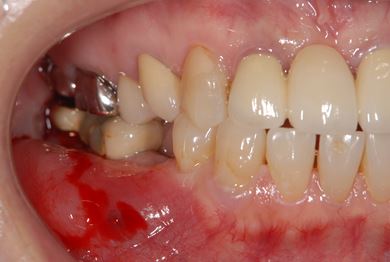

インプラントの症例写真 IMPLANT

骨再生スピードインプラント治療+セラミック治療

| 治療方針 | 骨再生法によりインプラント治療を可能にする。抜歯と同時にインプラント埋入を行い、治療期間を短縮する。 | ||||||||||||||||||||||||||||||||

| 治療内容 | インプラント3本(抜歯即日スピードインプラント、GBR)、メタルボンドセラミッククラウン4本 | ||||||||||||||||||||||||||||||||